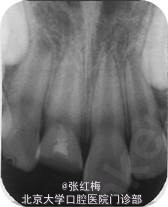

X线示:11、21发育9期,根管粗大,未见明显根折线,根尖周未见病变影,骨硬板清晰,未见牙槽突骨折线;

检查:11充填体完好,叩(-),不松,龈未见异常,X线:11根尖继续形成中,根周膜清 晰;

检查:11粘接断冠完好,叩(-),不松,龈未见异常,冷测有感觉,无疼痛;X线:11根 尖继续

形成中,根周膜清晰